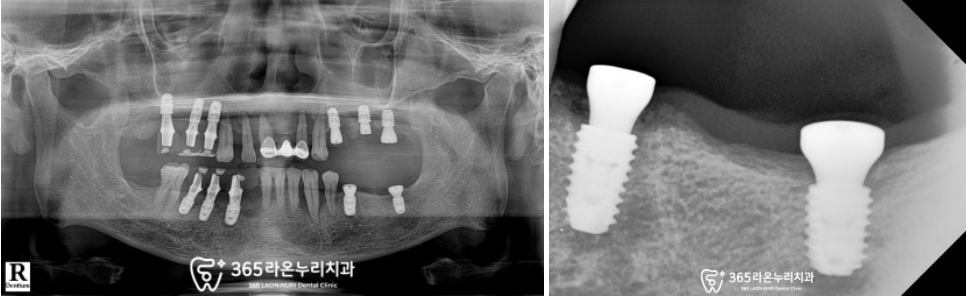

▮ 6. 최종 보철 수복

모든 진료가 끝난 모습을 보겠습니다.

전체적으로 적응 기간이 필요했기에

여러 번 제작과 조정을 거친 후

환자가 편안함을 느끼실 때까지

맞춰드리느라 시간은 좀 더 걸렸던 것 같네요.

그러나 보이는 것처럼

위아래 심미-저작 기능을 모두 회복하고

충분히 편안함을 느끼셨을 때

최종 보철을 올려드리는 게 맞다 생각했기에

환자와 충분히 기간을 조율하며

마무리해드렸습니다.